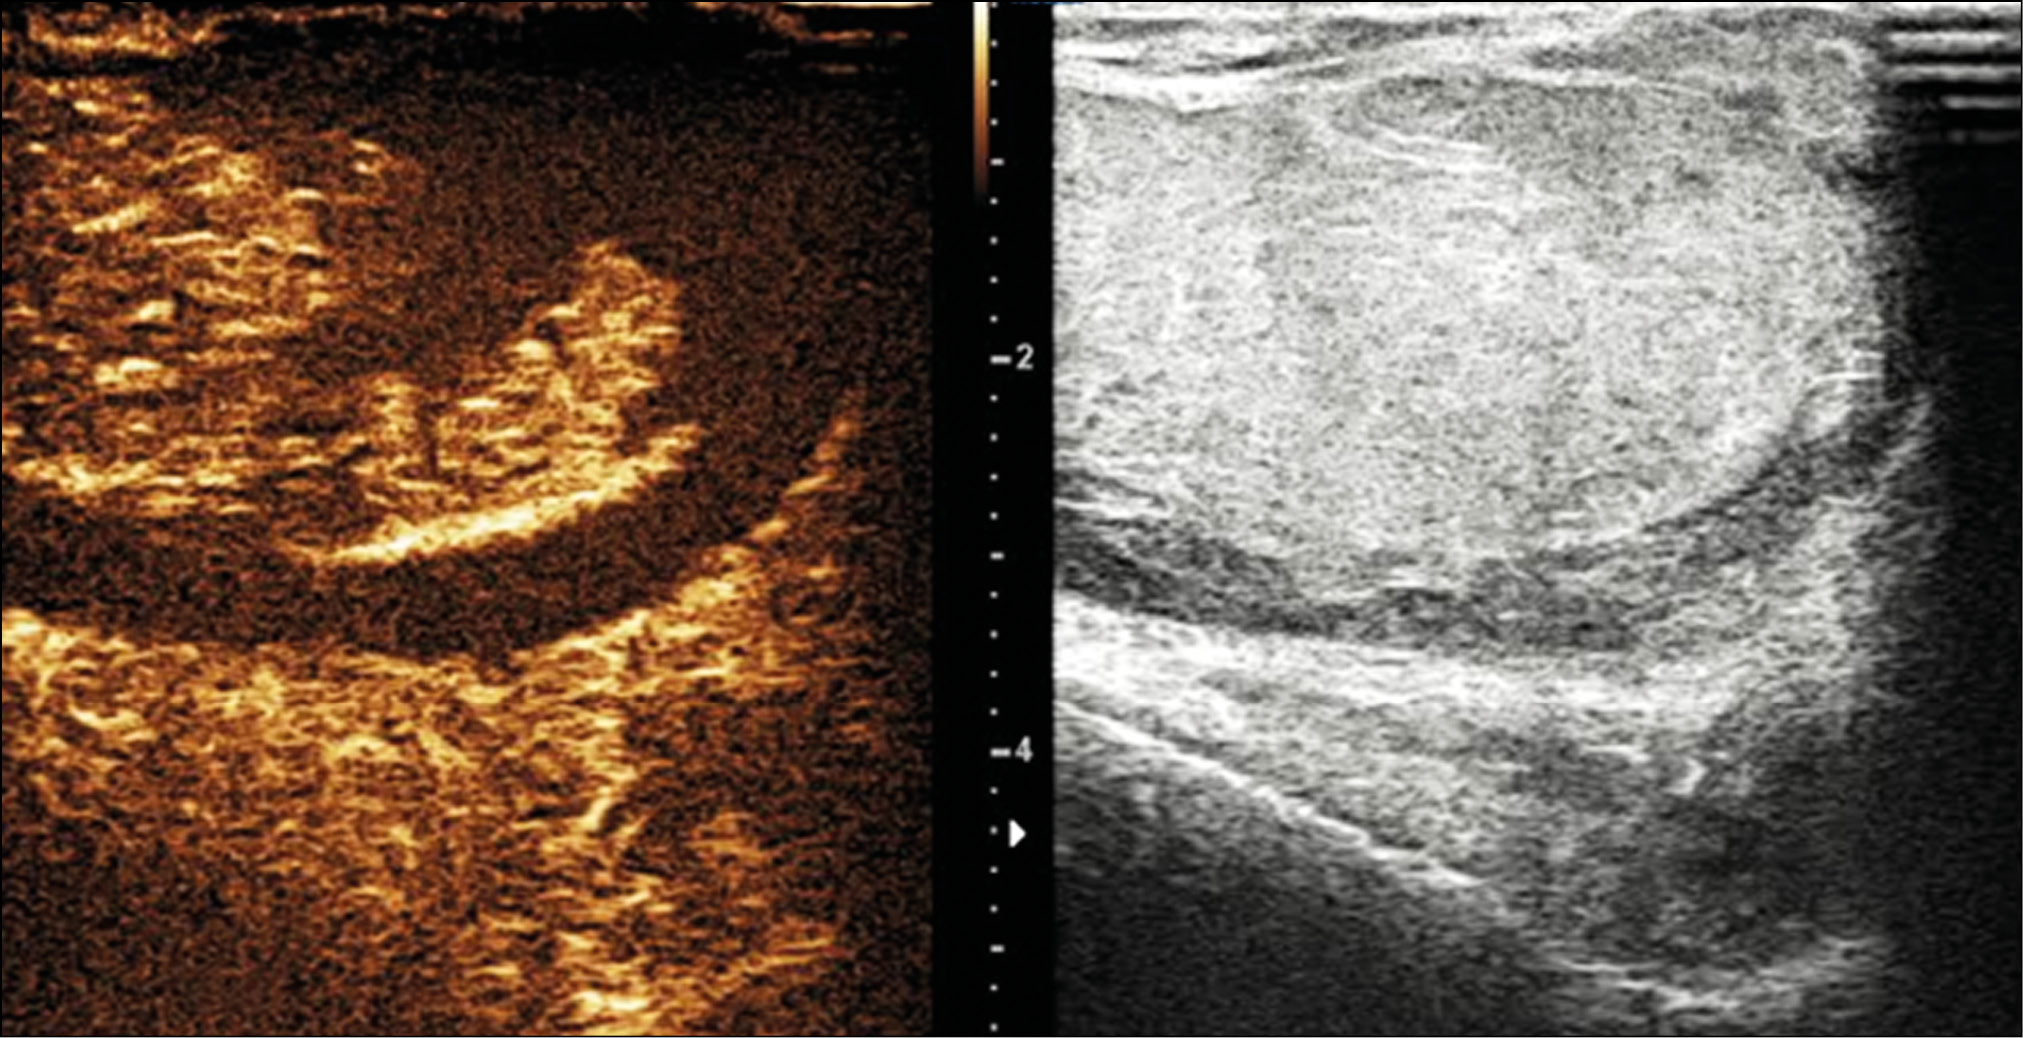

A healthy 15-year-old male teen was hit in the scrotum with a kick in the groin during a football match. He had an immediate and severe pain. After a few hours, although symptoms had improved, he presented to our emergency department with persistent swelling and purplish discoloration of the left scrotum. He did not report any other injuries. The genitourinary examination revealed that the left hemiscrotum was about two times larger than the right with severe ecchymosis. The left testicle was difficult to palpate because of pain and swelling, whereas the right testicle had a normal size and did not reveal any palpable abnormalities. The cremasteric reflex was not elicited on the left side. Scrotal ultrasonography (US) showed moderate scrotal edema and hematocele with a discontinuity in the tunica albuginea characterized by an abnormal contour (Figure 1). Color Doppler US (CDUS) documented a loss of vascularization in the upper pole that extruded into the broken portion of the testicle of approximately 2.5 cm (Figure 2) but no evidence of torsion or infarction. Urology consultation was requested, and a contrast-enhanced US (CEUS) was performed, which confirmed the diagnosis of testicular rupture and determined the amount of the vital parenchyma (Figure 3). The patient was hospitalized for urgent examination of the left hemiscotum based on the US results. During surgery, a large hematocele was evacuated, and a closer inspection of the testicle revealed a lesion of the tunica albuginea. Primary closure of the tunica was performed (Figure 4). The patient made an uneventful recovery, and he was discharged after 4 days.

Figure 3. Contrast-enhanced ultrasonography image determines the extent of vital parenchyma, helping in the preoperative decision-making process, and allows the recovery of vital testicular tissue, avoiding the need for orchidectomy.